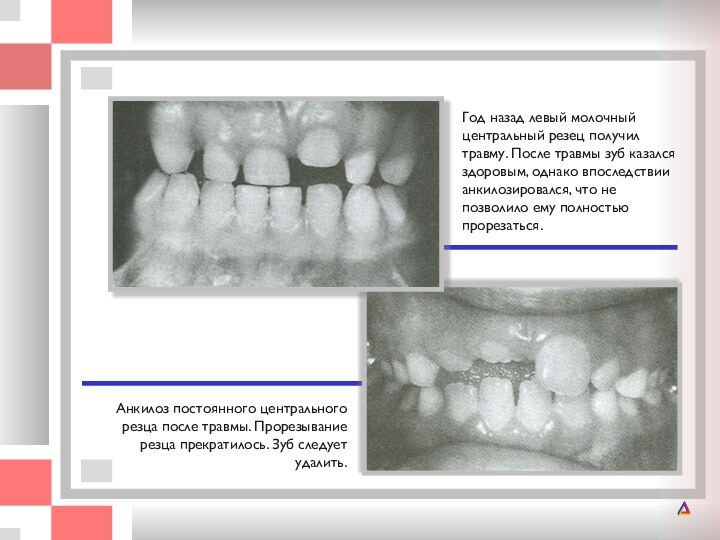

Год назад левый молочный центральный резец получил травму. После травмы зуб

После травмы зуб казался здоровым, однако впоследствии анкилозировался, что

не позволило ему полностью прорезаться.

Анкилоз постоянного центрального резца после травмы. Прорезывание резца прекратилось. Зуб следует удалить.